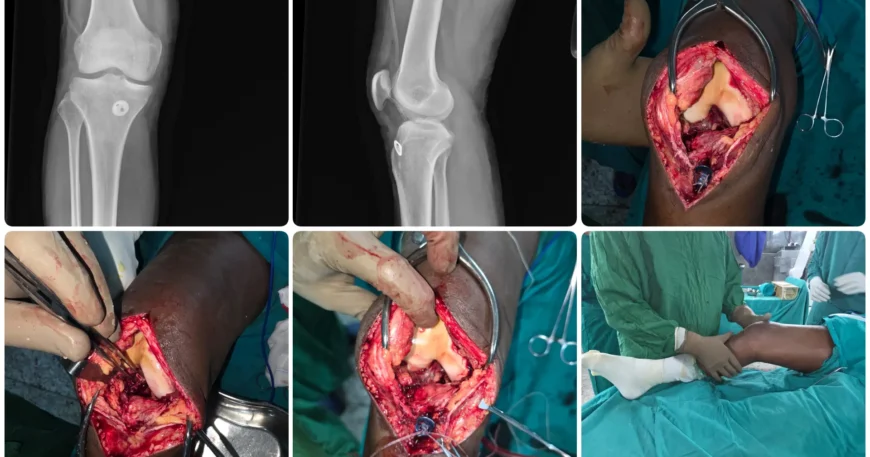

Clinical examination and imaging confirmed a complete tear of the right ACL, a common injury often caused by sports activities, sudden twisting movements, or trauma.

Arthroscopic ACL Reconstruction with Hamstring Graft

Mr. Akshay underwent arthroscopic ACL reconstruction using a hamstring tendon graft, a minimally invasive technique that offers excellent strength and long-term outcomes.

The torn ACL was replaced with a hamstring graft and securely fixed using advanced surgical devices under arthroscopic guidance.